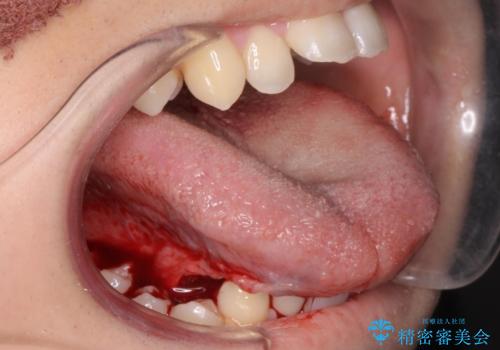

- 外科手術のため、術後に出血、痛みや腫れ、違和感を伴います

手術は当日に行う事ができ、一週間後に抜糸を行います。